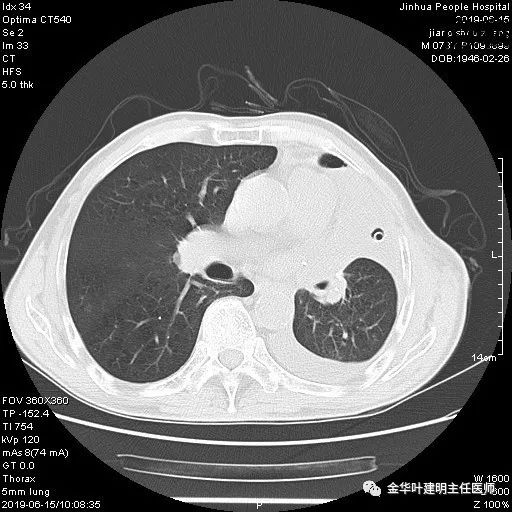

6.15上午:24小时胸管引流出血性液250ml;复查胸部CT示: